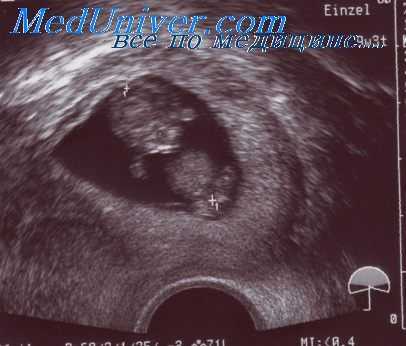

При ультразвуковом обследовании области тромбоза межворсинчатого пространства имеют вид анили гипоэхогенных внутриплацентарных включений, размер которых варьирует от нескольких миллиметров до нескольких сантиметров. Они могут простираться до хориальной или базальной пластинки.

При помощи эхографии такие изменения могут выявляться, начиная с 19 нед беременности. При резус-конфликте было отмечено повышение частоты выявления тромбоза межворсинчатого пространства, что позволяет предположить, что его наличие имеет отношение к развитию сенсибилизации.